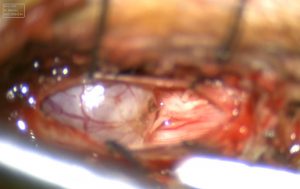

Η ασθενής υπεβλήθη σε πεταλοπλαστική Ο4-Ο5 και θυριδοποίηση διαμεσοτόξιου διαστήματος Ο1/2 από αριστερά και αφαίρεση και των δύο εξεργασιών, υπό συνεχή διεγχειρητικό νευροφυσιολογικό έλεγχο.

Οι λόγοι που επέλεξα να παρουσιάσω το περιστατικό αυτό είναι δύο. Ο πρώτος είναι για να δείξω ότι πολλαπλές βλάβες μπορούν να αντιμετωπιστούν με ασφάλεια και αποτελεσματικότητα σε ένα χρόνο, δηλ. σε ένα χειρουργείο. Αυτό στο οποίο θέλω κυρίως να εστιάσω είναι η προσπελάσεις που χρησιμοποιήθηκαν και συγκεκριμένα ο συνδυασμός της τεχνικής της πεταλοτομίας-πεταλοπλαστικής και της διαμεσοτόξιας θυριδοποίησης. Επιλέξαμε δηλαδή να μήν κάνουμε μια μεγάλη τομή και εκτεταμένη πεταλεκτομία αλλά να συνδυάσουμε δύο κομψές, ατραυματικές τεχνικές. Σε αντίθεση με την πεταλεκτομία, όπου τα οπίσθια στοιχεία (δηλ. ένα τμήμα της “ραχοκοκκαλιάς”) αφαιρούνται μόνιμα, στην πεταλοπλαστική τα πέταλα επανατοποθετούνται και οι σύνδεσμοι συρράφονται, επιτυγχάνοντας έτσι την αποκατάσταση της ανατομίας της σπονδυλικής στήλης. Αυτό έχει πολλαπλά οφέλη: δεν επηρεάζεται η σταθερότητα της σπονδυλικής στήλης, δε δημιουργείται ουλή πάνω στη μήνιγγα, μειώνεται σημαντικά το ποσοστό διαφυγής εγκεφαλονωτιαίου υγρού κ.α. Το ίδιο ισχύει και για τη θυριδοποίηση. Στη θυριδοποίηση, η διαμεσοτόξιος θυρίδα, δηλαδή ένα φυσικό άνοιγμα της σπονδυλικής στήλης επεκτείνεται και με μικροχειρουργικές τεχνικές αφαιρείται όλη η βλάβη.